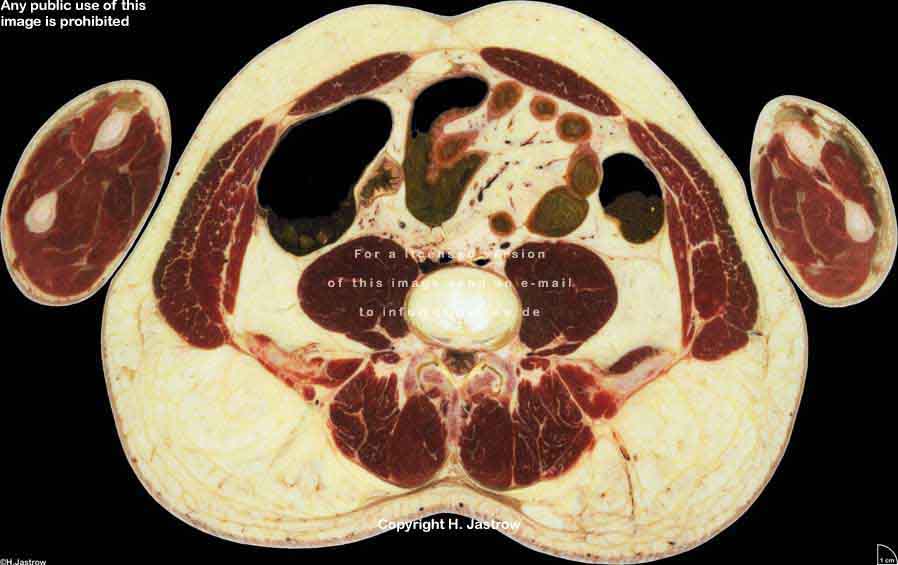

Visible Human male: Sectio transversalis 1733

CT

NMR

Pd                          / T2 \                         T1